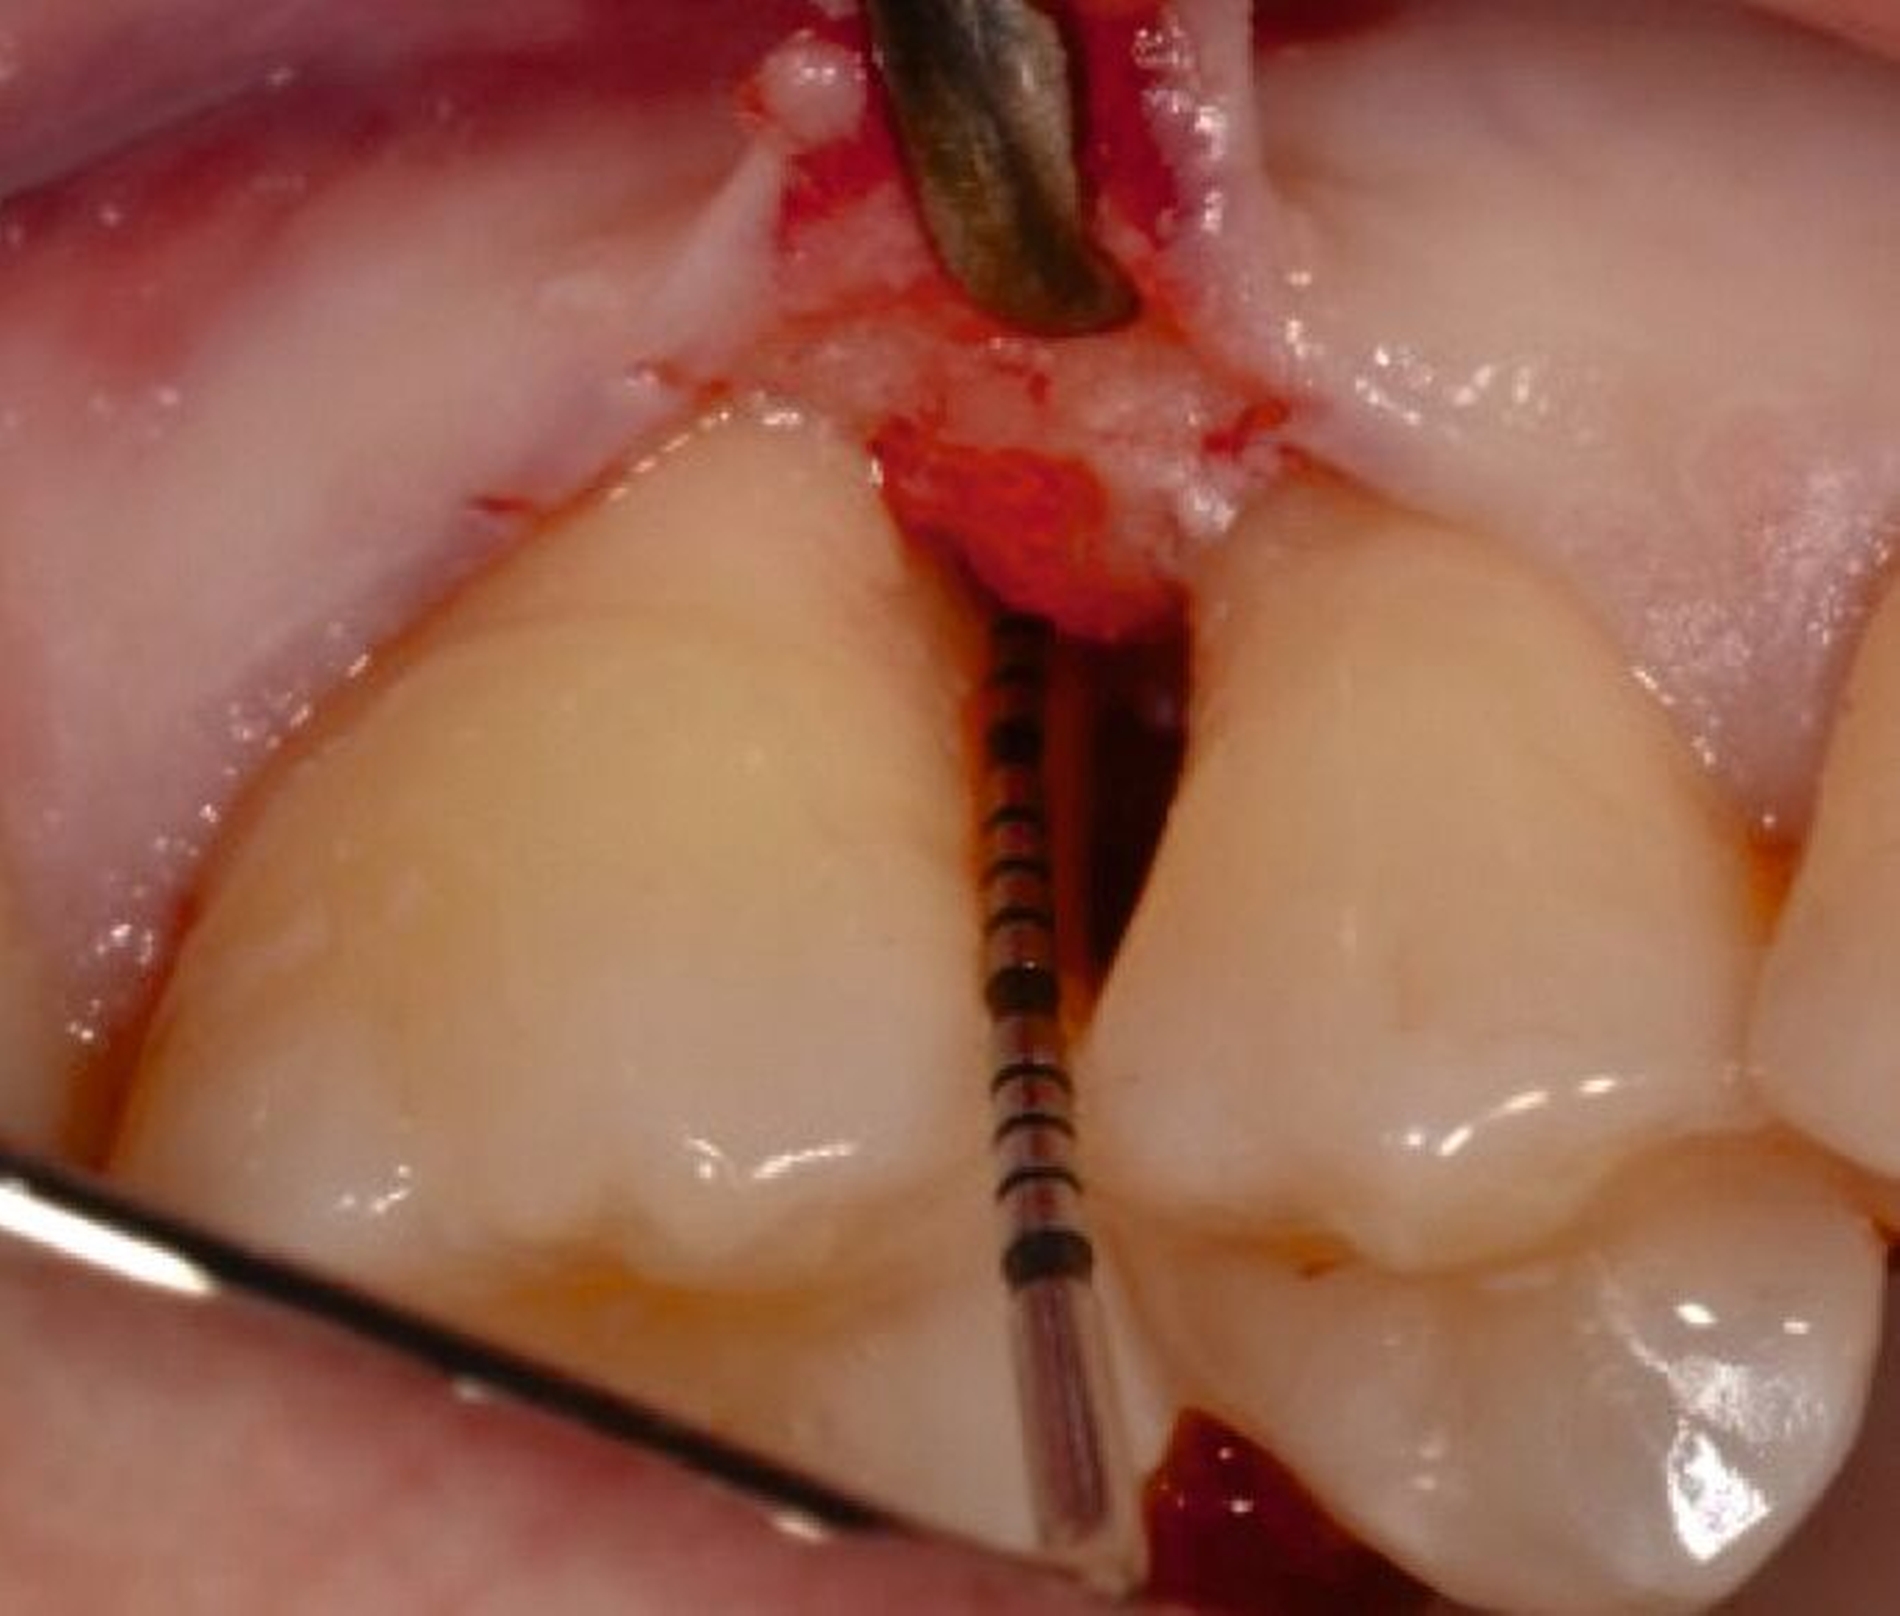

Ziel ist es, einen ausreichenden Zugang zum Defekt für eine sorgfältige Instrumentierung und die Applikation des Biomaterials zu erhalten. Bei isolierten Defekten können vertikale Entlastungsinzisionen verwendet werden. Alternativ kann der Lappen nach lateral zu den benachbarten Zähnen erweitert werden. Keratinisiertes Gewebe sollte durch intrasulkuläre Inzision und die Anhebung eines Mukoperiostlappens erhalten werden. Das Granulationsgewebe wird entfernt und die freiliegenden Wurzeloberflächen werden sorgfältig mit Handinstrumenten, oszillierenden Scalern (optional mit fein diamantierten Spitzen) oder rotierenden Instrumenten gereinigt. Wurzelanomalien wie Schmelzvorsprünge/-perlen sollten entfernt werden. Wenn EMD Teil der Regenerationsstrategie ist, wird es in der Regel nach einer zweiminütigen Wurzelkonditionierung mit Ethylendiamintetraacetat (EDTA) und Spülung mit steriler Kochsalzlösung angewendet. Anschließend kann ein Knochentransplantat/-ersatzmaterial verwendet werden, um den Furkationsdefekt aufzufüllen.

Alternativ kann eine GTR-Barrieremembran mit oder ohne zusätzlichen Defektfüller appliziert werden. Die Barrieremembran wird mit einer resorbierbaren Umschlingungsnaht befestigt, um den Furkationseingang abzudecken und die Wund- und Koagulumstabilisierung zu fördern. Um eine vollständige Abdeckung der Barriere zu ermöglichen, kann das Periost durchtrennt werden, um den Lappen leicht koronal zu verschieben. Der Lappen wird mit einer Umschlingungsnaht und Einzelknopfnähten über den vertikalen Entlastungsinzisionen oder mit interdentalen Nähten im Fall eines lateral extendierten Lappens in einer koronalen Position gesichert. Der Patient wird angewiesen, für einen Zeitraum von bis zu vier Wochen auf die mechanische Plaqueentfernung im Operationsgebiet zu verzichten. Während dieser Zeit werden Chlorhexidin-Spülungen oder -Gel verwendet. Der Patient kehrt zur Kontrolle der Wundheilung nach ein und zwei Wochen zurück, wenn die Nähte entfernt werden. Die Interdentalhygiene und die mechanische Plaqueentfernung werden nach vier Wochen wieder aufgenommen. Zudem wird ein individuelles Recallprogramm zur unterstützenden Parodontitistherapie (UPT) festgelegt.